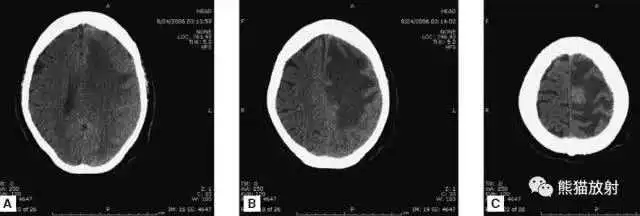

高血压性脑出血:

- 自发性出血;

- 继发于长期高血压及慢性血管病;

- 常见于基底节区、丘脑、脑桥、小脑。

A:占位效应,相邻脑沟、脑池消失;

F:脑出血破入四脑室。

▲

钩回疝:

是当代偿机制不能适应占位性病变时的结果。

基底节区大量高血压性脑出血,破入脑室及蛛网膜下腔,周围水肿,脑干周围空间消失;脑干出血、脑积水。